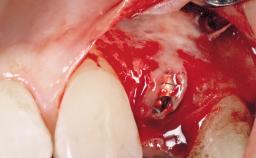

Immediate Flapless Placement of an Implant in a Maxillary Left Central Incisor Site

A 42-year-old female patient was referred to our clinic at the School of Dentistry of the University of São Paulo in November 2004, presenting a deficient restoration in the upper left central incisor. The clinical examination revealed no gingival retraction or any signs of gingival inflammation and, therefore, previous periodontal treatment was not considered. The patient presented a high lip line at full smile and a thin tissue biotype. This combination characterized a high-risk situation from an anatomic point of view, which required careful preoperative planning and cautious surgical execution.

Placement Protocol Immediate implant placement

Bone Volume Sufficient, with intact walls

Anatomic Risk Low

Esthetic Risk Medium